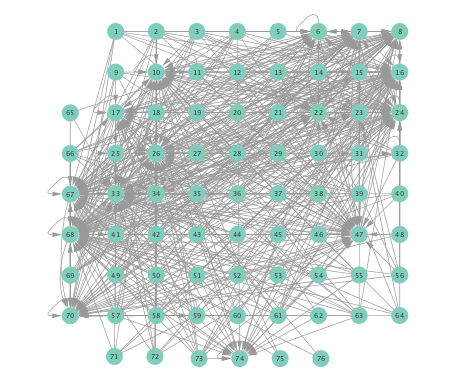

VI-B Inferred networks

Prior to running the developed algorithm, s intervals were chosen from the preprocessed ECoG data, and then divided into successive segments, each spanning s. To illustrate this, suppose the s interval starts from s and ends at , then the first segment comprises samples taken over the interval , the second one would be , and so on. After this segmentation of the time series, directed network topologies were inferred using Algorithm 1 with , based on the s segments, instead of the entire signal, to ensure that the signal is approximately stationary per experiment run. A directed link from electrode to was drawn if at least one of the estimates of turned out to be nonzero.

Networks inferred from the preictal and ictal intervals were compared using the linear, the kernel-based (K-)SVARMs, as well as the K-SVARM with data-driven kernel selection. The lag lengths were set to for all cases. For the K-SVARM, a polynomial kernel of order was selected. Furthermore, the threshold in Algorithm 1 was set to , was set to , while the regularization parameter was selected via cross-validation. For the data-driven kernel selection scheme, two candidate kernels were employed, namely, a linear kernel, and a polynomial kernel of order .

Figure 2 depicts networks inferred from different algorithms for both preictal and ictal intervals of the time series. The figure illustrates results obtained by the linear SVARM, and the K-SVARM approach with and without kernel selection. Each node in the network is representative of an electrode, and it is depicted as a circle, while the node arrangement is forced to remain consistent across the four visual representations. A cursory inspection of the visual maps reveals significant variations in connectivity patterns between ictal and preictal intervals for both models. Specifically, networks inferred via the K-SVARMs, reveal a global decrease in the number of links emanating from each node, while those inferred via the linear model depict increases and decreases in links connected to different nodes. Interestingly, the K-SVARM with kernel selection recovered most of the edges inferred by the linear and the K-SVARM using a polynomial kernel, which implies that both linear and nonlinear interactions may exist in brain networks. Clearly, one is unlikely to gain much insight only by visual inspection of the network topologies. To further analyze differences between inferred networks from both models, and to assess the potential benefits gained by adopting the novel scheme, several network topology metrics are computed and compared in the next subsection.